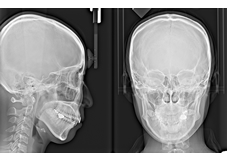

セファロ画像

当医院では、精度の高い治療を行うために最新鋭の歯科用CT『AUGE SOLIO』を導入しています。従来のレントゲンでは、平面での診断しかできませんでしたがCTでは3次元的に立体画像

で確認ができる為、骨の厚みや神経までの距離、血管の位置など正確に把握することができます。

歯科用CTは、医科用のCTとは異なり歯科用にカスタマイズされたもので放射線量は10分の1以下になっており、低被爆線量で安全に撮影することができます。